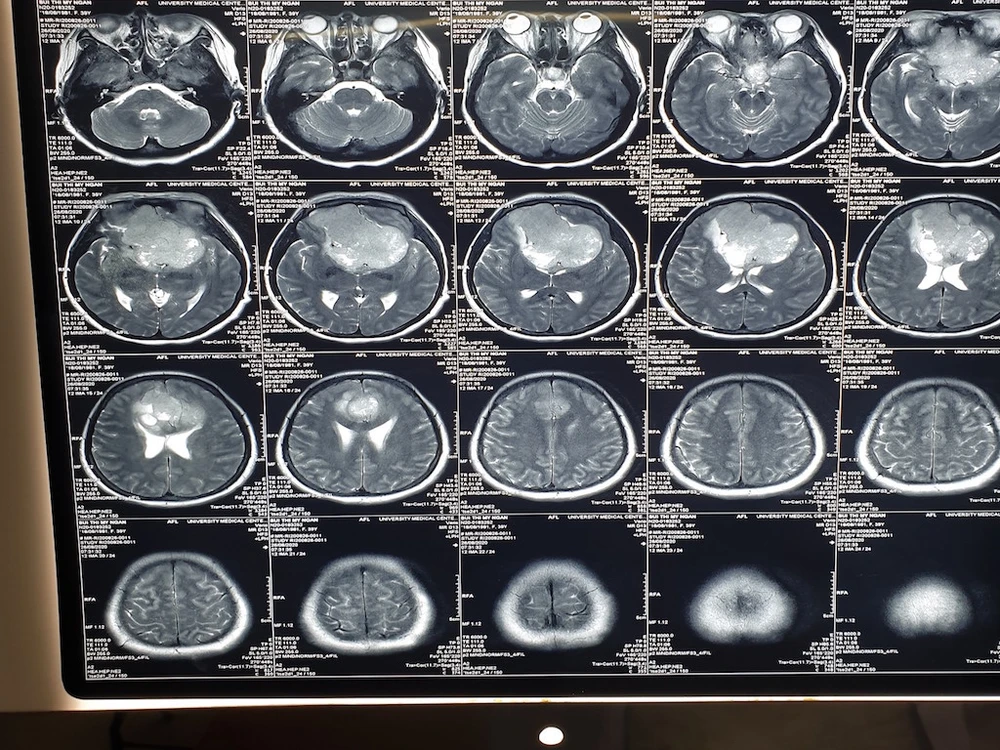

Khối u qua ảnh chụp MRI và các bác sĩ đang tiến hành phẫu thuật cắt khối u qua kính hiển vi. Ảnh: HD 1 Khối u qua ảnh chụp MRI và các bác sĩ đang tiến hành phẫu thuật cắt khối u qua kính hiển vi. Ảnh: HD 2

Khối u qua ảnh chụp MRI và các bác sĩ đang tiến hành phẫu thuật cắt khối u qua kính hiển vi. Ảnh: HD

Kết quả chẩn đoán hình ảnh cho thấy bệnh nhân bị u màng não nền sọ kích thước 7x9,5 cm. U không xâm lấn nhưng dính vào các mạch máu lớn, trong quá trình phẫu thuật dễ gây tổn thương các mạch máu gây khó khăn trong phẫu thuật.